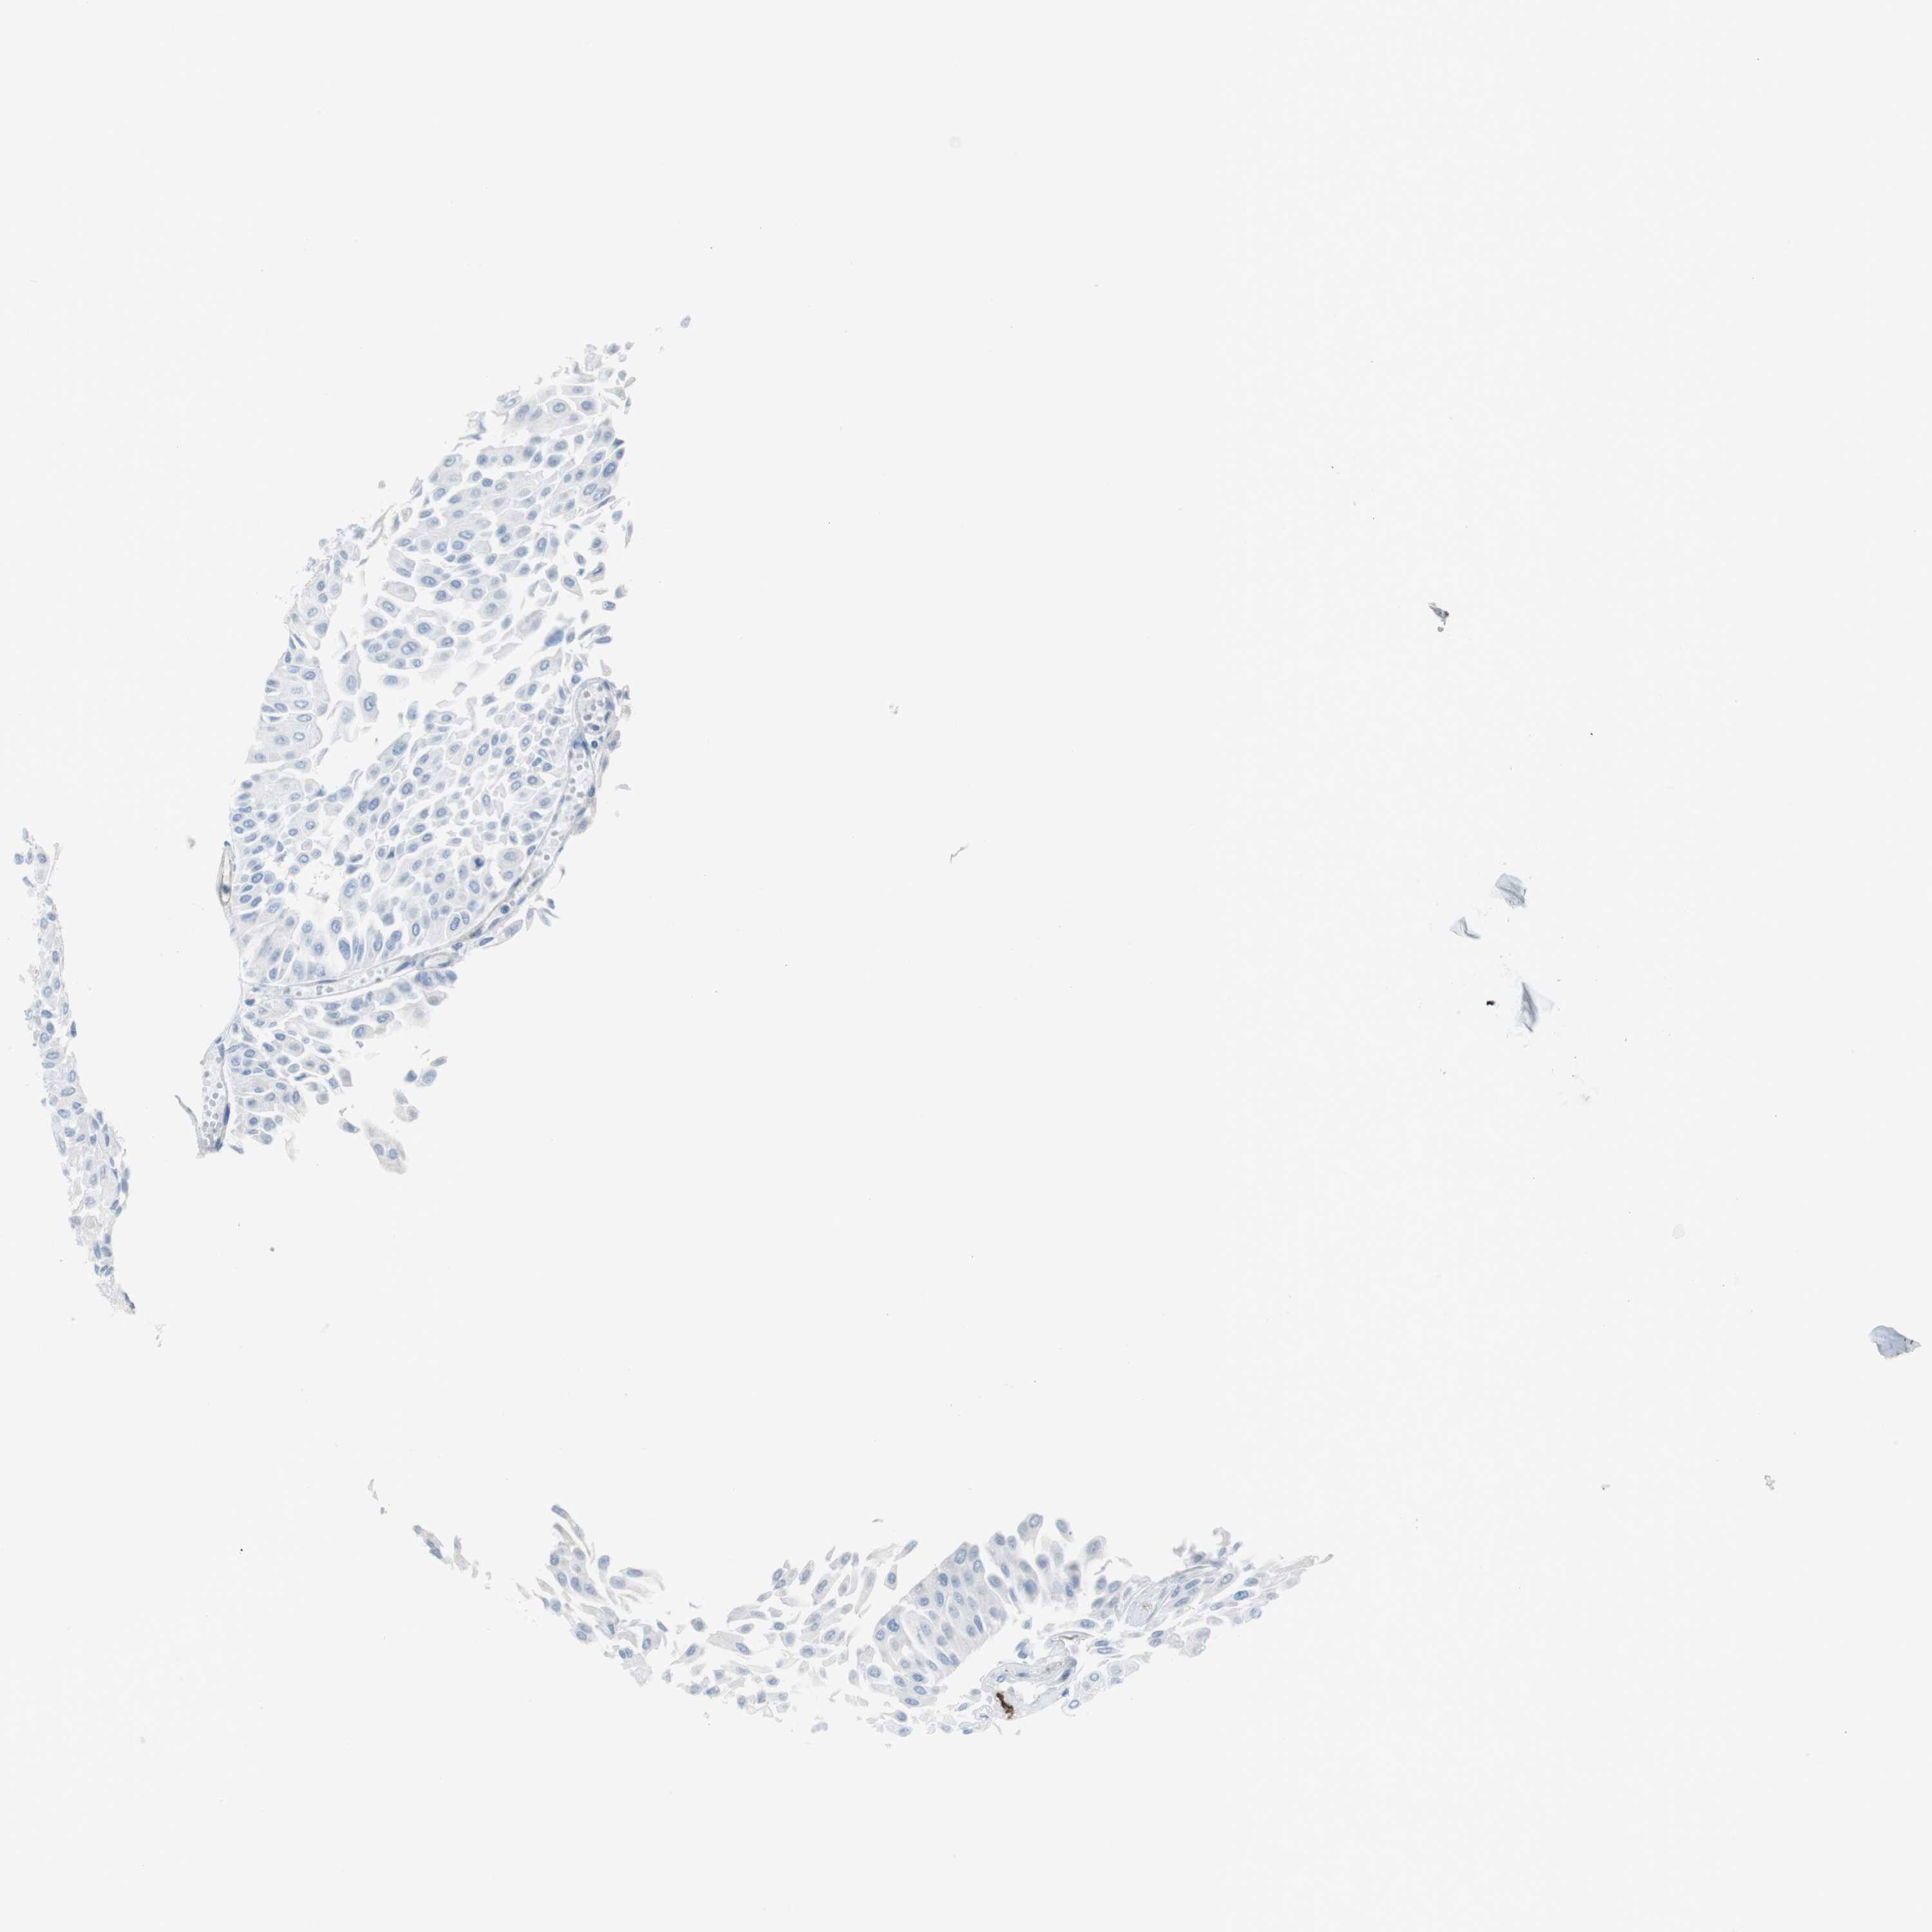

UROTHELIAL CANCER - Protein expressioni

A mouse-over function shows sample information and annotation data. Click on an image to view it in a full screen mode. Samples can be filtered based on level of antibody staining by selecting one or several of the following categories: high, medium, low and not detected. The assay and annotation is described here.

Note that samples used for immunohistochemistry by the Human Protein Atlas do not correspond to samples in the TCGA dataset.

Antibody stainingi

Antibody staining in the annotated cell types in the current human tissue is reported as not detected, low, medium, or high, based on conventional immunohistochemistry profiling in selected tissues. This score is based on the combination of the staining intensity and fraction of stained cells.

Each image is clickable and will lead to virtual microscopy that enables deeper exploration of all samples and also displays staining intensity scores, fraction scores and subcellular localization as well as patient and tissue information for each sample.

Antibody HPA043640

Antibody HPA046280

Antibody CAB015339

Urothelial carcinoma, High grade

Urothelial carcinoma, Low grade